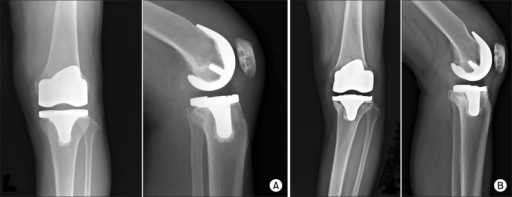

Aflojamiento aséptico / Aseptic loosening

Aflojamiento aséptico

Aseptic loosening

De manera general se dice que existe el aflojamiento aséptico cuando se genera el aflojamiento de los componentes de algún implante o prótesis.

Aseptic loosening is a common condition that occurs due to the failure of the bone and implant interface, used in joint replacement therapy such as total hip arthroplasty.

Aflojamiento séptico | Aflojamiento aséptico de prótesis de rodilla | Aflojamiento mecánico Septic loosening | Knee prosthesis aseptic loosening | Mechanic loosening

Un total de 96 artroplastias de 127 completaron el seguimiento. La media de edad fue de 79 años. La media de seguimiento fue de 14,5 años. Once prótesis se reintervinieron (6 por aflojamiento aséptico de implantes y 5 por problemas de componentes móviles).

At 15 years’ follow-up, 33 of 458 (7.2%) TKRs were revised for aseptic loosening. Kaplan-Meier survival analysis showed a weak tendency towards improved survival with restoration of a neutral mechanical axis, but this did not reach statistical significance (p = 0.47).